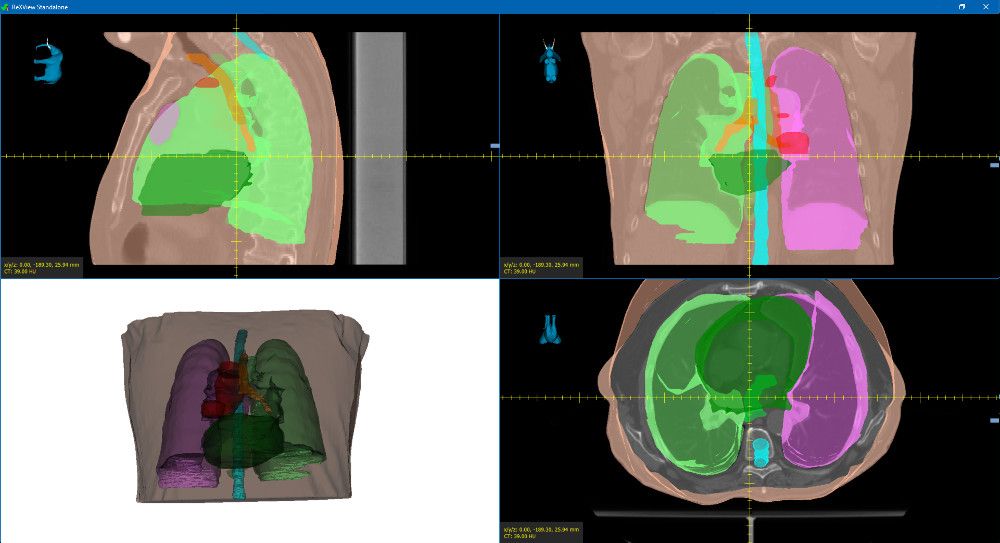

Gemeinsam mit MedPhoton haben wir ReXView (Reconstruction und X-ray Viewer) entwickelt. ReXView ermöglicht die Visualisierung und den Vergleich volumetrischer 3D-Daten und 2D-Projektdaten.

Mit Hilfe verschiedener Messwerkzeuge ist es möglich, Bilddaten präzise zu analysieren. Zusätzlich können Bilder mit 3D-Objekten (zum Beispiel inneren Organen) überlagert werden. Dadurch ermöglicht ReXViewer eine detaillierte Diagnose der Patientendaten, die von geschulten Radiologen erstellt werden kann.